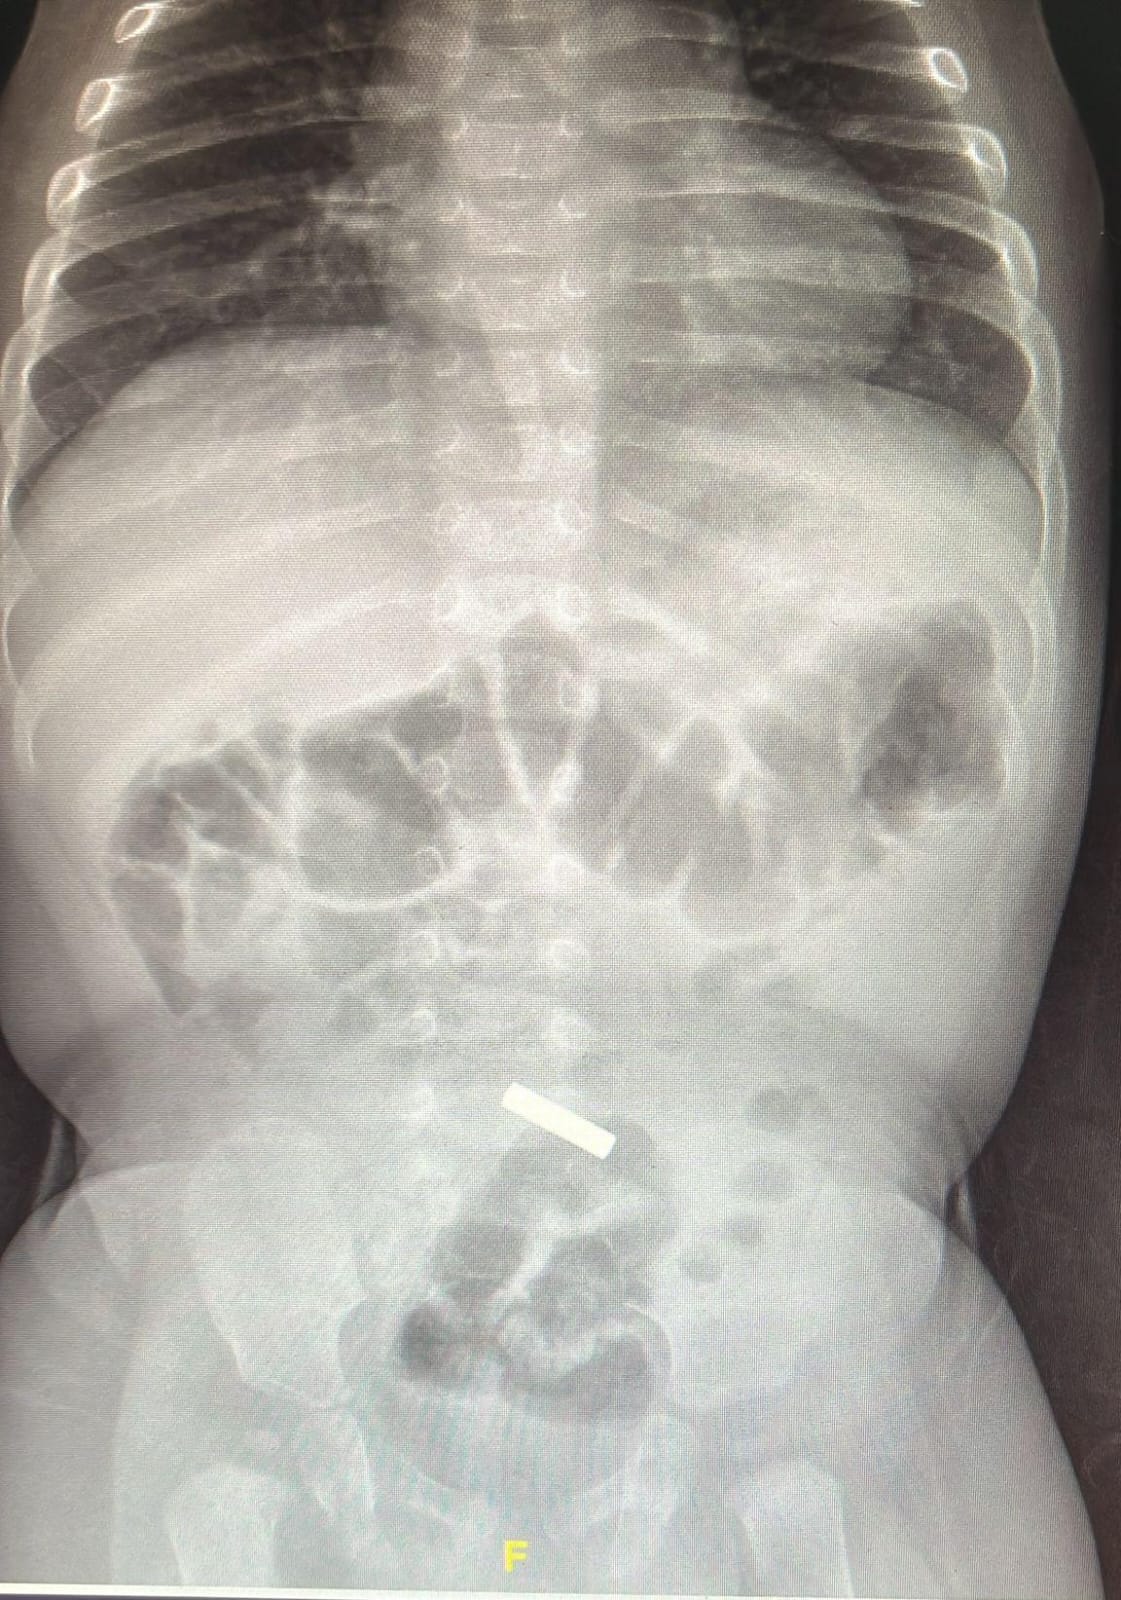

اهلا- كريستين مهاشه د. سعيد أبو زيد من المركز الطبي "تسفون": نواكب ارتفاع في حالات إصابات الأولاد جراء ابتلاع قطع وأغراض غريبة وصل الى المركز الطبي "تسفون" بوريا طفل يبلغ من العمر 11 شهرا بعد ان لاحظ اهل الطفل انه يعاني من درجة حرارة عالية وتقيؤ. وقد خضع الطفل للفحوصات اللازمة في قسم الأطفال في المركز الطبي، واتضح بعد اجراء تصوير اشعة للطفل انه على ما يبدو ابتلع قطعة معدنية استقرت في الأمعاء الدقيقة. وقد تلقى الطفل العلاج الفوري من حيث الأدوية والسوائل بهدف خفض درجة حرارته، كما تم اخضاعه لفحوصات أخرى عديدة أخرى. وتحدث الدكتور سعيد أبو زيد مدير قسم الأطفال في المركز الطبي "تسفون" مشيرا الى ان الطفل على ما يبدو عانى من الحمى الشديدة والتقيؤ بسبب مرض فيروسي، لكن يتم أيضاً فحص احتمال أن يكون الجسم الغريب الذي ابتلعه هو الذي تسبب في ضرر موضعي أدى إلى ذلك. وأضاف د. أبو زيد مشيرا الى ان ابتلاع الأغراض الصغيرة تعتبر خطيرة جدا على حياة الأطفال بما في ذلك ابتلاع القطع المعدنية وخاصة البطاريات الصغيرة والتي تؤدي الى مخاطر عديدة. فإذا علقت هذه القطع الغريبة في المريء فإنها من الممكن ان تتسبب بجراح وبالتالي تؤدي الى التهاب شديد وخطير، وفي هذه الحالة لا بد من إزالة الجسم الغريب فوراً. ومع ذلك، في هذه الحالة، كانت القطعة المعدنية قد مرت بالفعل عبر المريء وتم العثور عليها في منطقة الأمعاء. لهذا نحن الآن كطاقم طبي أكثر اطمئنانا ونتوقع أنها ستخرج في اليوم التالي دون الحاجة لأي تدخل طبي". واختتم د. أبو زيد حديثه مشيرا الى انه في الآونة الأخيرة نلاحظ ارتفاع حقيقي في عدد الحالات التي تصل الينا الى المركز الطبي لأطفال كانوا قد ابتلعوا قطع مختلفة منها المعدنية وغيرها وهنا تكمن أهمية ابعاد هذه الأغراض عن متناول يد الأطفال والعمل على مراقبتهم بشكل دائم من قبل الأهل منعا لإصابتهم. الصورة المرفقة تصوير المركز الطبي تسفون